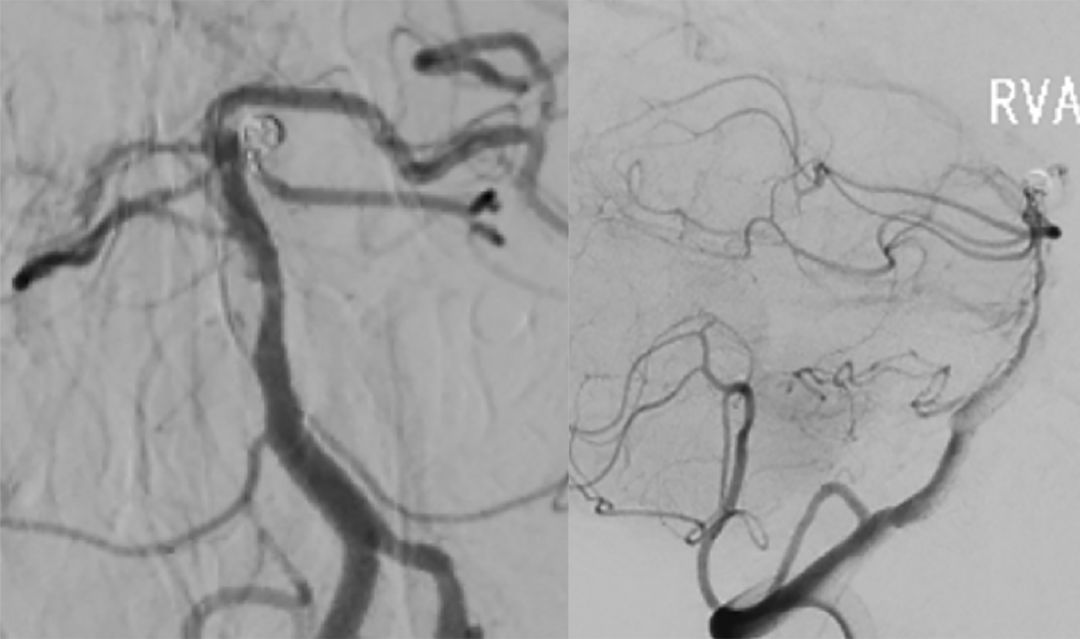

6. 多个投射角度辅助下,将数枚弹簧圈枚植入动脉瘤内(图12)。

图12

7. 术后造影显示动脉瘤完全栓塞,载瘤动脉通畅(图13)。

图13